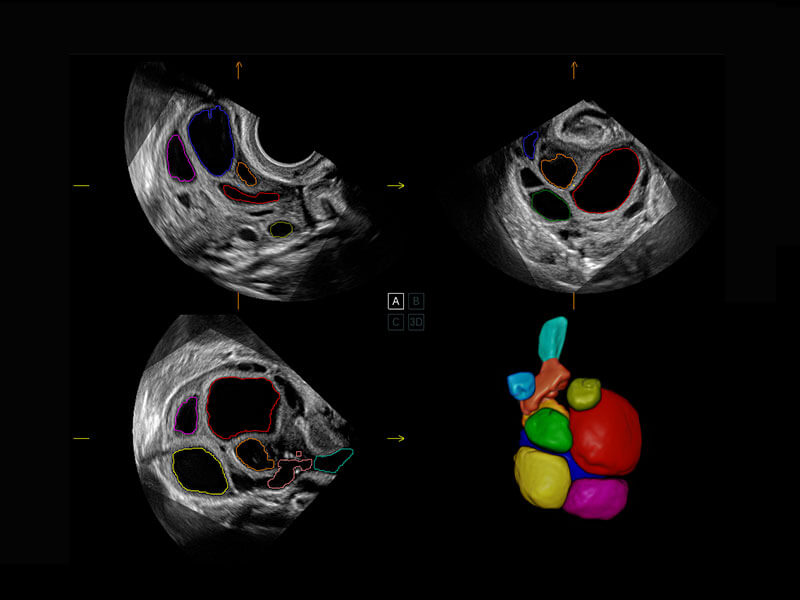

P60搭载一系列胎儿心脏成像技术,实现精细的胎儿心脏评估。

右室双出口

胎心容积成像